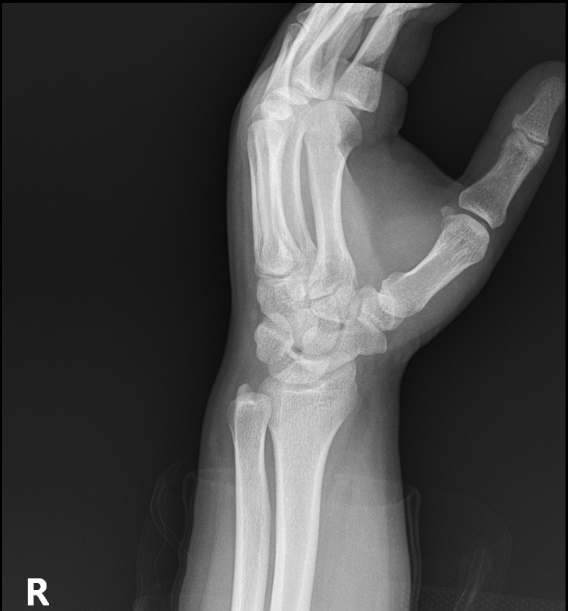

우측 손목 바깥쪽 척골 근처 통증으로 처음엔 힘줄염 진단받고 소염진통제 3개월 먹고 체외충격파 여러번 받았는데도 좋아지지 않아서 mri찍었습니다. mri상 힘줄은 전혀 염증이 없고 tfcc쪽 상태가 아주 깨끗하진 않지만(다 검정색이어야하는데) 아주 나쁘고 그렇지도 않다고 들었어요. 그래서 좀 찾아보니 척골충돌증후군하고 증상이 비슷해서 혹시 사진상 척골충돌증후군에 해당되는지 여쭈어봅니다.

엑스레이상 척골이 과하게 길어서 생기는 충돌증후군은 없습니다.